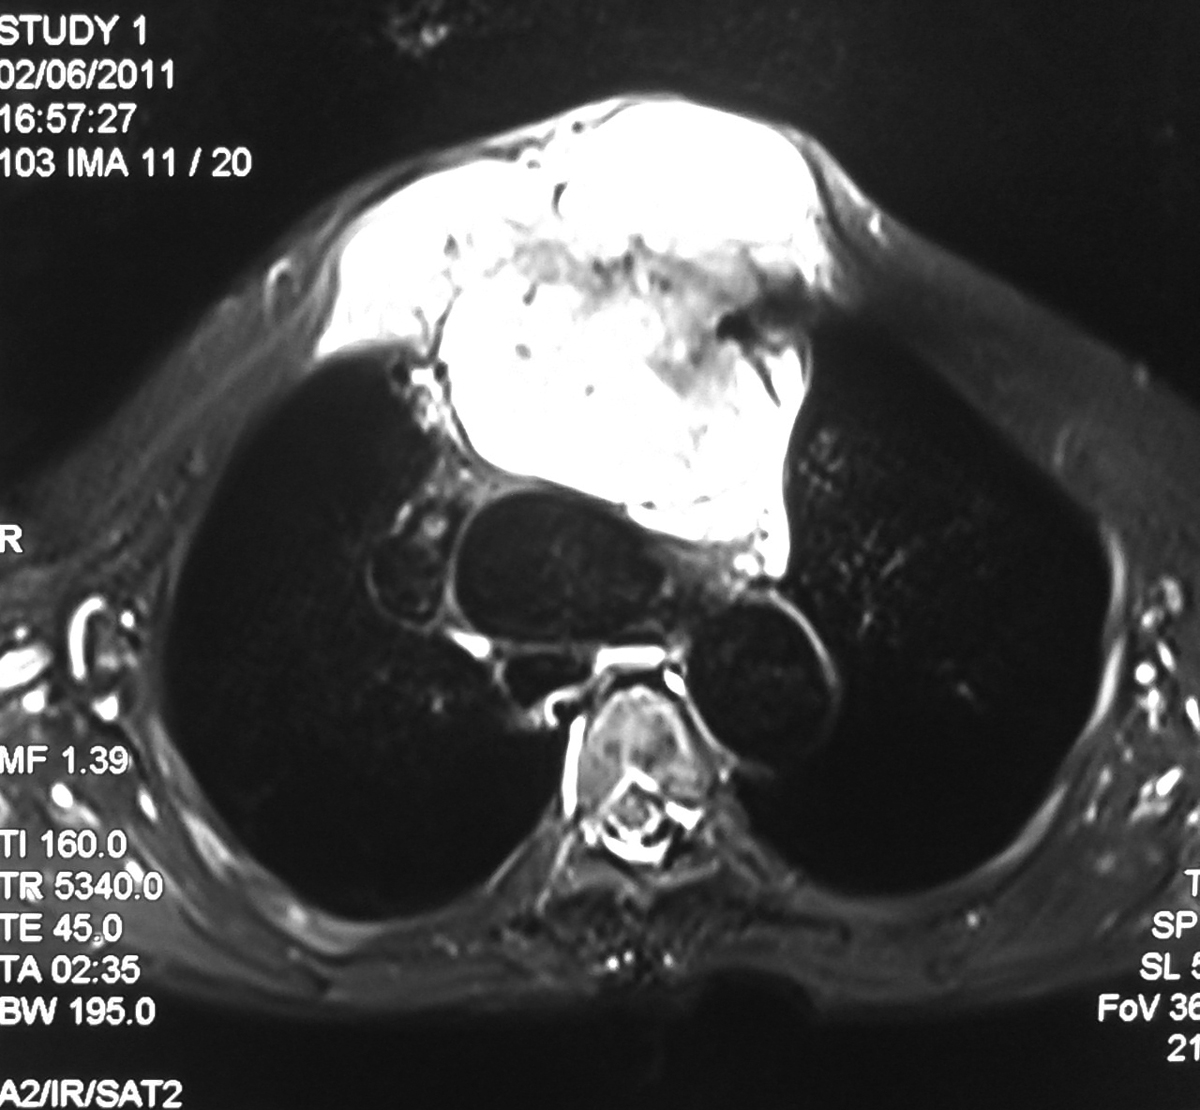

32 Year old male with road traffic accident showing posterior dislocation of the elbow joint with mild proximal migration of the radius and ulna and small displaced chip fracture of the coronoid process.

MRI sagittal T2 images showing posterior dislocated elbow.